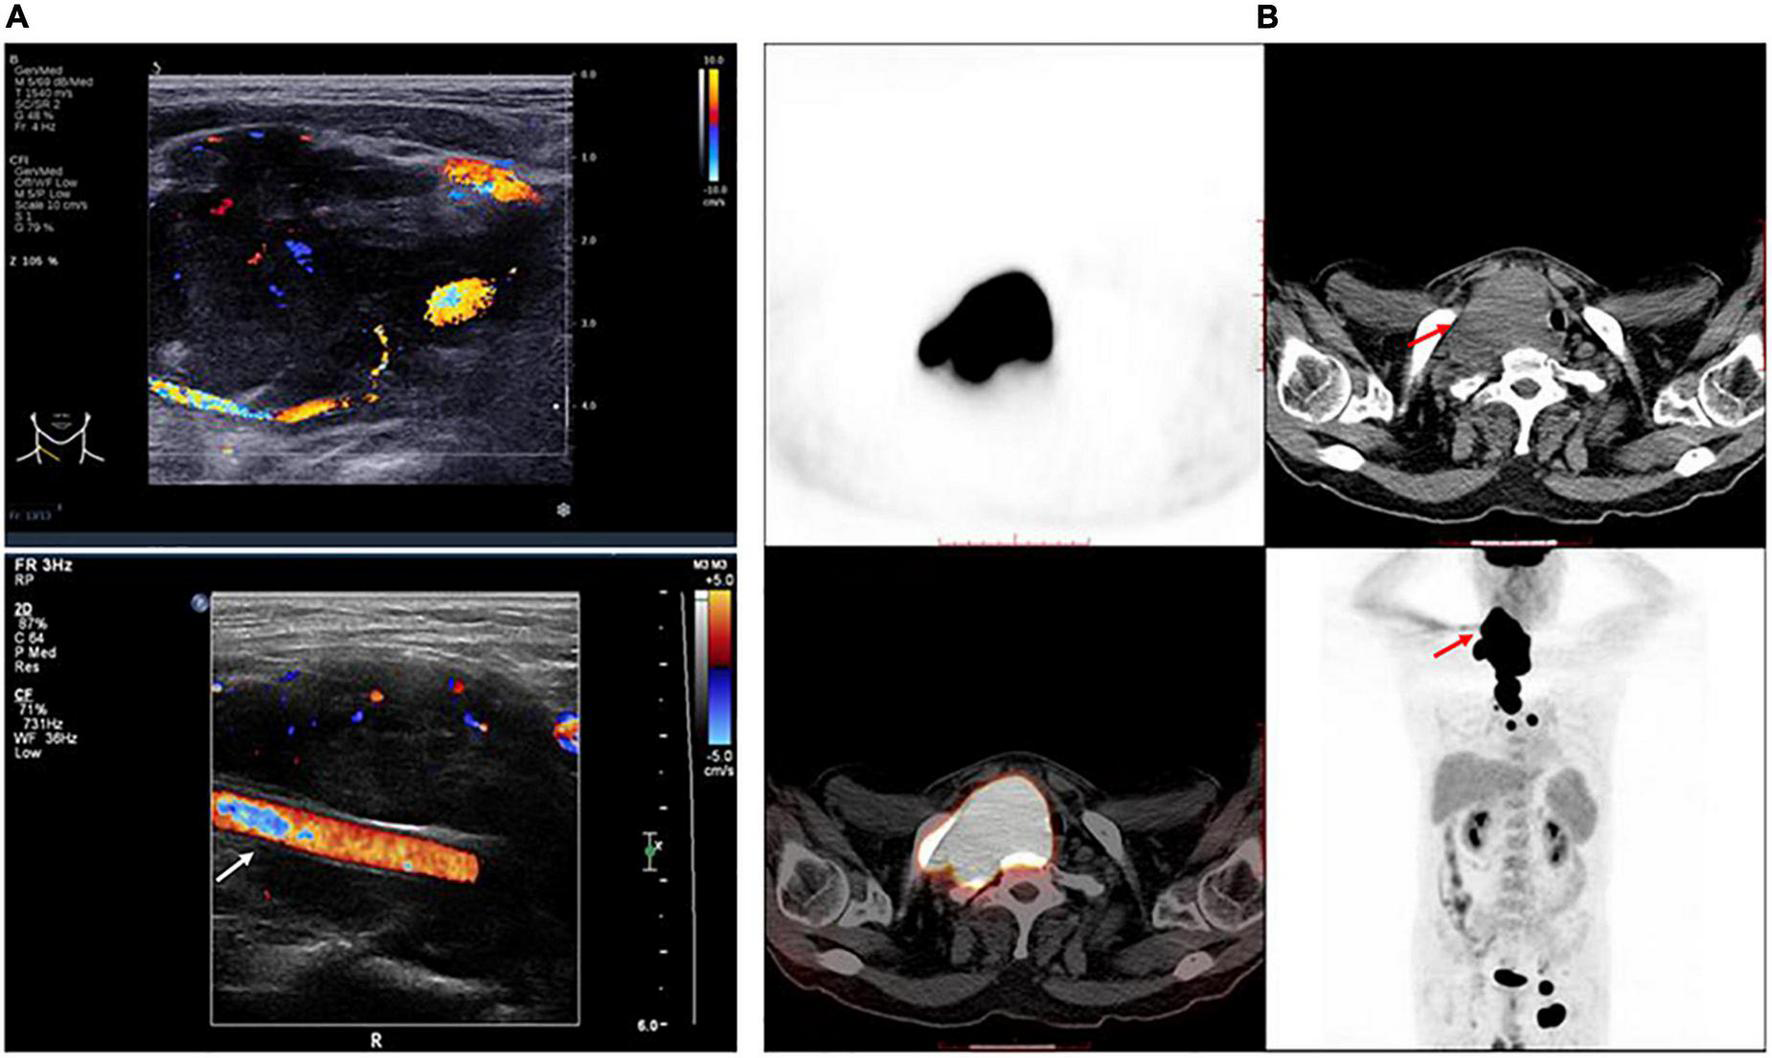

Neck ultrasonography showed a hypo-echoic region with abundant blood flow in the lower middle part of the right neck, approximately 9.0 cm × 8.2 cm × 4.4 cm, surrounding the right common carotid artery, which had normal internal blood flow (Figure 1A). Positron emission tomography (PET)/CT showed a large soft tissue mass in the right neck, approximately 8.6 cm × 5.0 cm × 11.0 cm, surrounding the adjacent large vessels (Figure 1B). The mass had a non-uniform increase in radioactive uptake, with a maximum standard uptake value (SUVmax) of 59.1. Lymph nodes in the right neck (SUVmax, 30.6), in the left hilar and mediastinal regions (SUVmax, 5.3–48.6), and along the left external iliac vessels and bilateral inguinal vessels (especially left inguinal) (SUVmax 2.3–43.2) demonstrated increased metabolism. Due to the high bleeding risk of the right neck mass, the left inguinal lymph node was biopsied instead. Histopathological examination showed highly invasive B-cell lymphoma with a morphology consistent with diffuse large B-cell lymphoma (Figure 2).

FIGURE 1

Features of the tumor. (A) Right neck ultrasonography shows a hypo-echoic region with abundant blood flow surrounding the right common carotid artery, which has normal internal blood flow. White arrow indicates the right common carotid artery. (B) The trunk positron emission tomography/computed tomography shows a large mass in the right neck surrounding the adjacent large vessels, which had a non-uniform increase in radioactive uptake. Red arrow indicates the tumor.